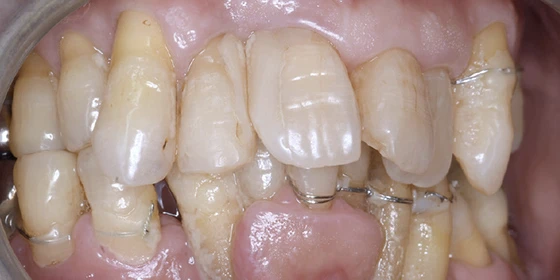

治療前

この症例では下顎の歯周病が特に進行していて、歯がクラグラで噛みにくい為、下の歯を抜歯してオールオン4で治療、上は特に歯周病が進行している左側の大臼歯を抜歯して経過観察することにしました。